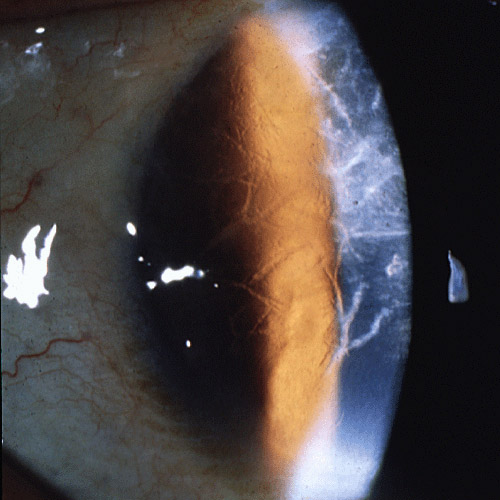

type III 는 상염색체 열성으로 나타나며,

40세 이후 발병하며, 시력저하는 60세 이후 늦게 나타납니다.

각막에는 굵은 형태의 선 침착이 나타나며, 각막 진무름은 발생하지 않습니다.